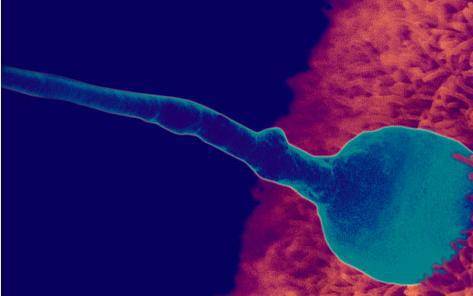

受孕

当精子遇到卵子结合的时候,受孕发生了。此时,基因构成已经完成,包括胎儿的性别。在受孕后约三天内,受精卵很快分裂成许多细胞。它通过输卵管进入子宫,在那里它附着在子宫壁上。你的胎宝宝开始了生命旅程。